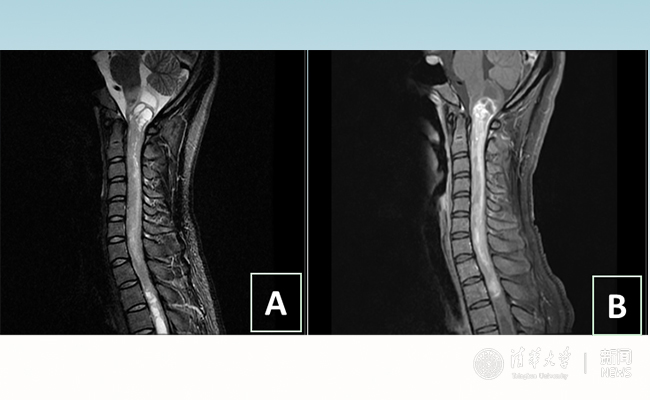

2018.01拯救“90后”女孩 清华长庚神经外科切除20多公分髓内肿瘤

“愿得韶华刹那,开得满树芳华。”27岁的患者小甜(化名)在mk手机注册附属北京清华长庚医院成功进行了手术,神经外科主任王贵怀为其切除了自延髓至胸髓的长达20余公分的脊髓内肿瘤。1月9日,小甜顺利出院,再续芳华!